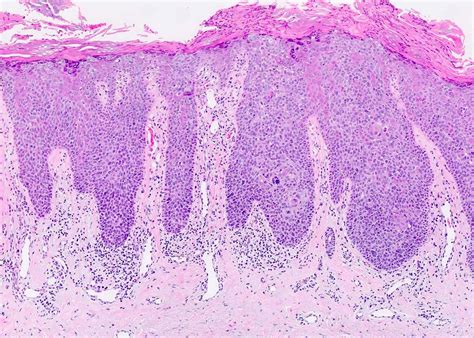

Enfermedad de Bowen, also known as Bowen's disease, is a rare skin condition characterized by the presence of slow-growing, reddish-brown plaques on the skin. This condition is typically caused by the human papillomavirus (HPV) and is considered a form of squamous cell carcinoma in situ. Understanding the symptoms, causes, diagnosis, and treatment options for Enfermedad de Bowen is crucial for effective management and prevention of complications.

Enfermedad de Bowen is a chronic skin condition that primarily affects the epidermis, the outermost layer of the skin. It is often mistaken for other skin conditions due to its similar appearance. The disease is more common in older adults, particularly those over the age of 60, and is slightly more prevalent in men than in women. The exact cause of Enfermedad de Bowen is not fully understood, but it is strongly associated with HPV infection, particularly types 16 and 18.

Diagnosing Enfermedad de Bowen typically involves a combination of clinical examination and laboratory tests. A healthcare provider will perform a physical examination of the affected area and may order a biopsy to confirm the diagnosis. A biopsy involves removing a small sample of the affected skin for microscopic examination. This helps to differentiate Enfermedad de Bowen from other skin conditions, such as psoriasis or eczema.